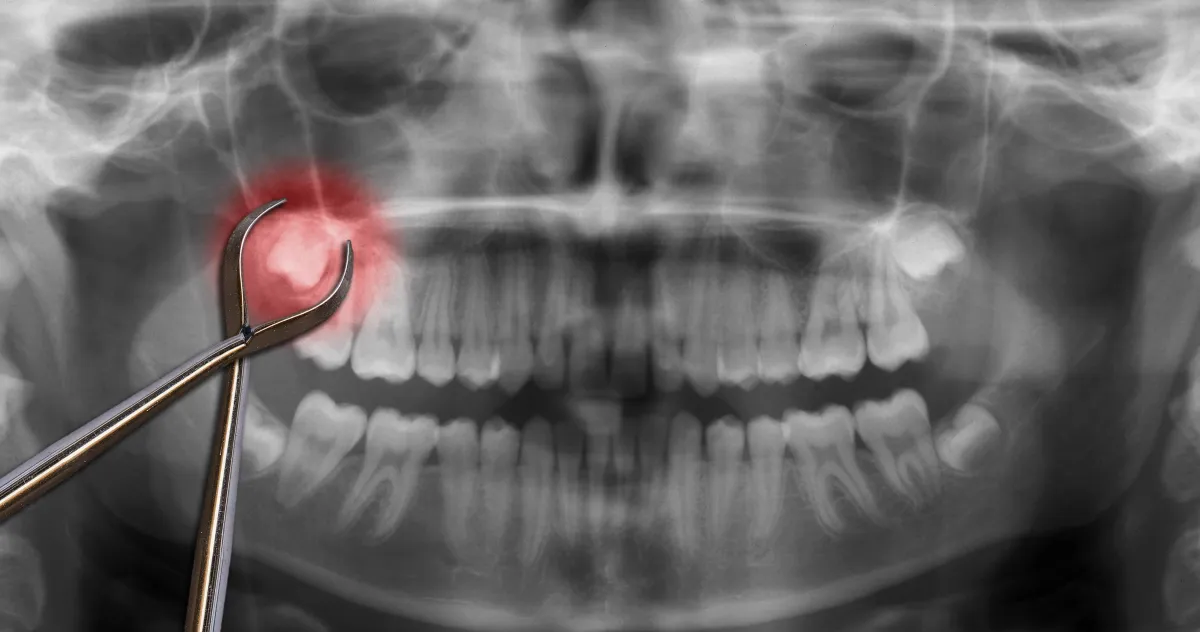

Yes — emergency tooth extractions are available 24/7 in Spokane. When a tooth is too damaged or infected to save, a careful extraction ends the pain and protects your health. We place you with the next‑available dentist for same‑day care.

Severe infection with bone loss

Impacted wisdom tooth causing repeated inflammation